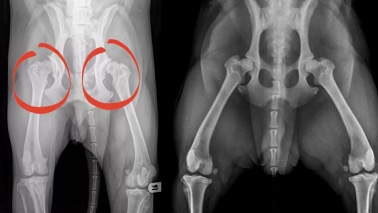

Dysplasie de la Hanche chez le Chien

Dysplasie de la Hanche chez le chien : Guide complet pour comprendre et agir